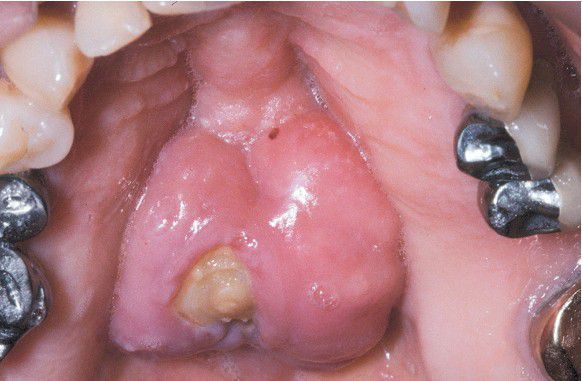

Medication-related Osteonecrosis

. Lobulated palatal torus with an area of exposed necrotic bone in a patient taking alendronate for osteoporosis.